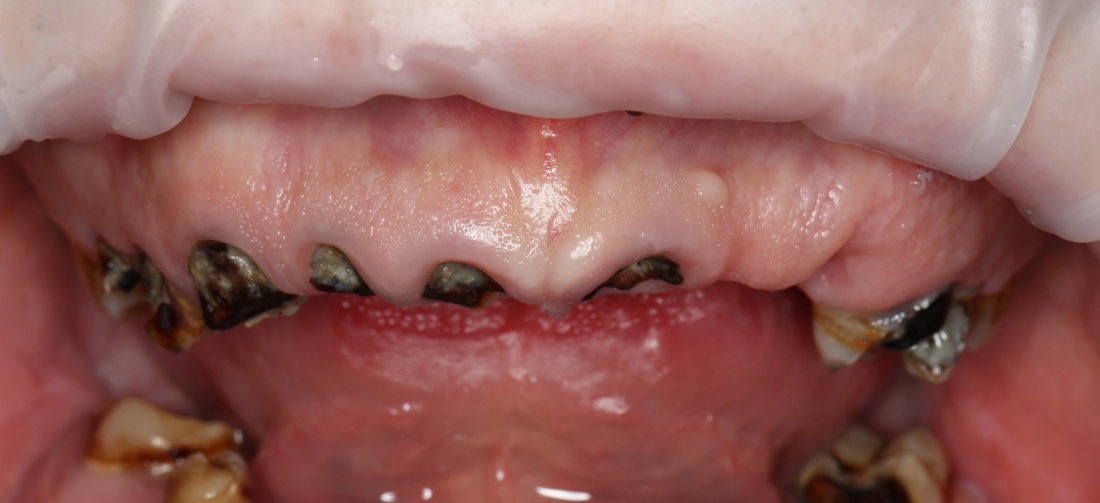

Один из них — 45-летний мужчина, который, буквально, потерял все зубы разом из-за пародонтита.

Второй пациент — 80-летняя бабушка, большую часть своей жизни пользующаяся полным съёмным протезом. Какие имплантологические решения мы им предложим и от чего они будут зависеть? Ведь вариантов достаточно много.

Наверное, 45-летний мужчина будет жаловаться на то, что внешность изменилась, ни разговаривать, ни улыбаться невозможно, девчонки его не любят, а он только что женился/развелся, у него только жизнь начинается, а тут такое… И, как мне кажется, он ожидает, что стоматолог ему сделает зубы даже лучше тех, что у него были, по всем параметрам.